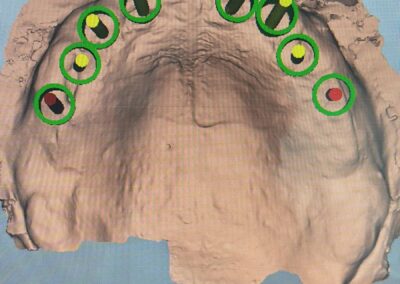

Ein entscheidender Bestandteil dieser modernen Praxis ist die Auswertung von 3D-Daten, die aus der Computertomographie extrahiert werden. Neuere Entwicklungen zeigen auch, dass Daten von optischen Scannern zunehmend in den Planungsprozess integriert werden. Diese umfassenden Informationen, kombiniert mit fortschrittlicher Implantatplanungssoftware, ermöglichen eine akkurate Simulation sowohl chirurgischer als auch prothetischer Phasen.

Vor der eigentlichen Operation können Implantatpositionen sorgfältig festgelegt werden, wobei spezifische Faktoren wie das Knochenvolumen und die -qualitäten, die Lage anatomischer Strukturen (wie Nerven, Gefäße und Nebenhöhlen), prothetische und ästhetische Bewertungen sowie präzise Messungen der Breite und Höhe des Knochens an den vorgesehenen Implantatstellen berücksichtigt werden. Auch die Abstände und Winkel zwischen den Implantaten lassen sich exakt berechnen, was entscheidend für den langfristigen Erfolg der Behandlung ist.

Bilder v.l.n.r.: 01 Herstellung der röntgenopaken Schablone zur Übertragung auf den Dicom-Datensatz / 02 Planung der Zahnimplantatstellung anhand der röntgenopaken Schablone / 03 Virtuelle Planung auf dem 3D-Modell / 04 Übertragung der Röntgenschablone auf dem Dicom-Datensatz (1:1) / 05 Virtuelle Plaung im Dicom-Datensatz / 06 Visualisierung frontal / 07 Visualisierung seitlich / 08 Visualisierung des Implantat-Falles frontal / 09 Visualisierung mit Bohrschablone